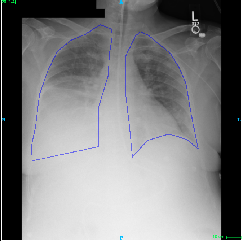

Fig.Β 5: Examples of class activation maps of positive cases. Left to right: image with annotation in blue, no L1 regularization, with L1 regularization, baseline.

Fig. 5 shows examples of class activation maps of positive cases for visual comparisons among the final models. These were produced using the Grad-CAM approach [14]. The images were annotated by an expert for the regions of opacity. Although all models correctly classified the cases as positives, the activation maps of the baseline model were barely correlated with the annotated regions, with more irrelevant hot spots outside the lungs. On the other hand, the activation maps of the models with feature selections were better correlated with the annotation. In other words, these smaller networks seems to be also more focused on the correct regions, which is a step towards explainability. The image in the third row shows that the VGG16 activation map has important components outside the lungs, focusing on English characters on the image. Whereas the reduced networks show more activation in marked areas of the lungs.